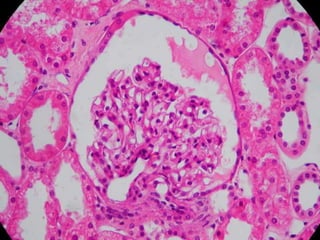

NÉFRONS - HISTOLOGIA

Glomérulo;

 Arteríolas aferente e eferente

ramificadas.

Cápsula de Bowman;

 Folheto parietal  tecido epitelial

simples pavimentoso.

 Folheto visceral  tecido epitelial

simples pavimentoso (podócitos). 11

Podócitos

 Células do folheto visceral;

 Tecido epitelial simples pavimentoso;

 Aderidas à membrana

basal dos capilares

glomerulares.